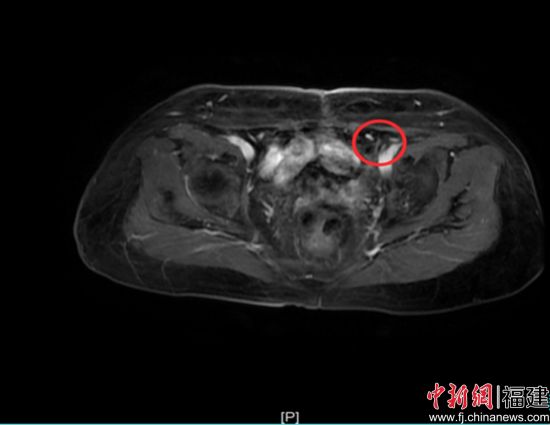

治疗过程顺利,相关指标逐步好转。用药2周期后,疗效评价即达到部分缓解(PR);用药6周期后,疗效评估进一步提升,达到完全缓解(CR)。更令人欣慰的是,整个治疗过程中患者耐受性良好,未出现严重血液学毒性及胃肠道反应,生活质量得到有效保障。目前,患者仍在维持用药中,持续受益于该治疗方案。